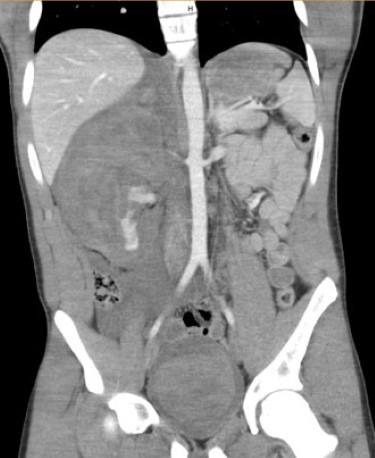

Case 4

A 16-year-old male presents with acute hematuria and abdominal pain after being checked with a lacrosse stick during practice. He is hemodynamically stable with a heart rate of 58. A FAST exam is performed by the treating clinician within 15 minutes of arrival to the pediatric emergency department. On FAST examination, there is free fluid in the right upper quadrant, and a mass is visible at the edge of the liver where the kidney is expected to be seen (Video 7). On the suprapubic view, the bladder contains a large echogenic clot (Video 8). Immediate surgical consultation and a CT scan confirm the presence of a large retroperitoneal hematoma with extravasation (Figure 3). The patient requires urgent operative intervention and nephrectomy.

Figure 3

Case 4 emphasizes the FAST exam's ability to detect complex injuries, such as a retroperitoneal hematoma and a bladder clot, leading to life-saving surgical treatment.

Together, these cases underscore the importance of recognizing that with current advancements in ultrasound technology for pediatric trauma care, the detection of injuries beyond the initial scope of the FAST exam is possible. In addition, the rapid findings obtained by performing the FAST exam expediated care, provided confidence in the need to obtain CT scans and surgical consultations, and helped alleviate the cognitive burden associated with disposition and other timely management decisions.